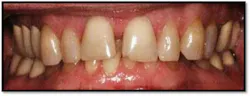

Pockets 4-7mm, generalized posterior BOP

UR/LR Pre TxThe tissues around the posterior crowns are almost bluish in color(above left)UL/LL Pre Tx: